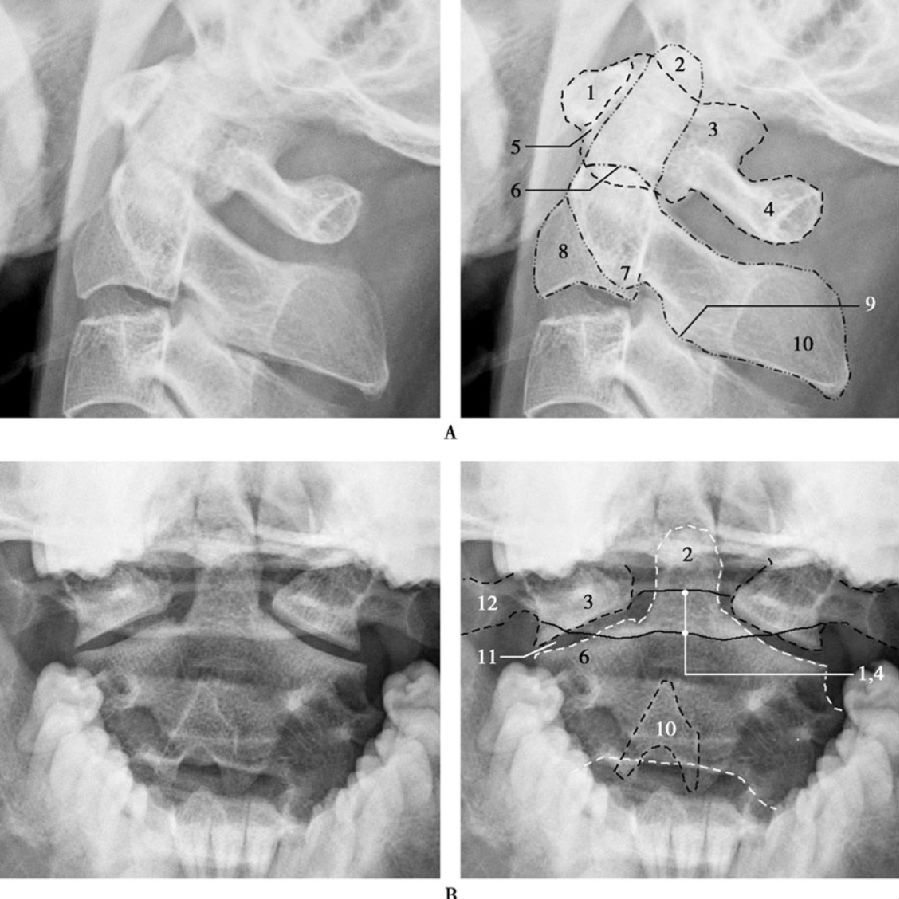

侧位片上,枢椎体部向上伸展形成齿突。寰椎前弓后缘阴影与齿突前缘间形成的间隙称为寰齿前间隙。寰椎前弓前缘阴影投影于其他颈椎总的曲度线之前。枢椎棘突影特别宽大,可作为阅片时颈椎计数的标志(图1)。

颈椎张口位可较满意地观察寰枢椎关节间隙、寰椎侧块和齿突。寰枢椎投影于上下齿列之间,齿突居中央,位于寰椎两侧下关节面最外缘连线的中垂线(寰椎轴线)上。齿突与寰枢椎侧块之间的间隙两侧对称(图1)。

图1 成人寰枢椎侧位(A)及张口位(B)

1. 寰椎前弓;2. 枢椎齿突;3. 寰椎侧块;4. 寰椎后弓;5. 寰齿前间隙;6. 枢椎上关节突;7. 枢椎横突;8. 枢椎椎体;9.枢椎下关节突;10. 枢椎棘突;11. 寰枢外侧关节;12. 寰椎横突。